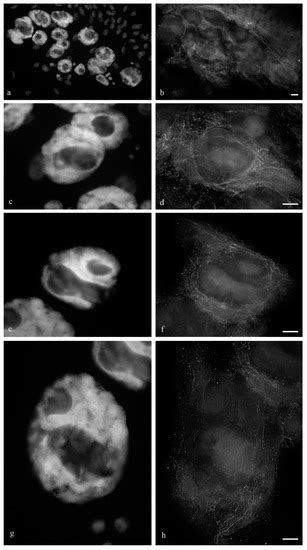

IKKγ/NEMO Localization into Multivesicular Bodies